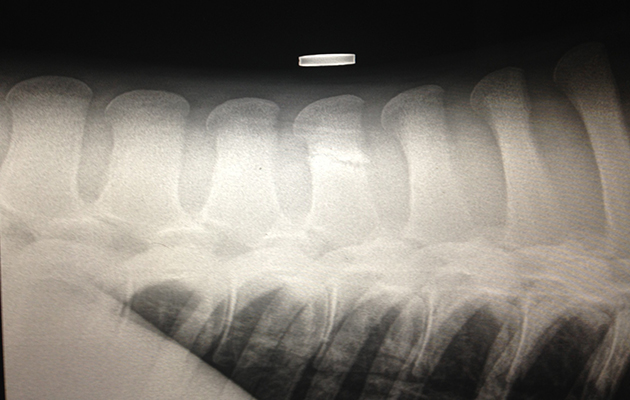

X-rays showed he had two vertebrae fractures — one in his spine and one in his neck.

Twiglets X-ray (3)“The injuries are consistent with a blunt trauma,” said vet Carys Chadwick from B&W Equine Group.